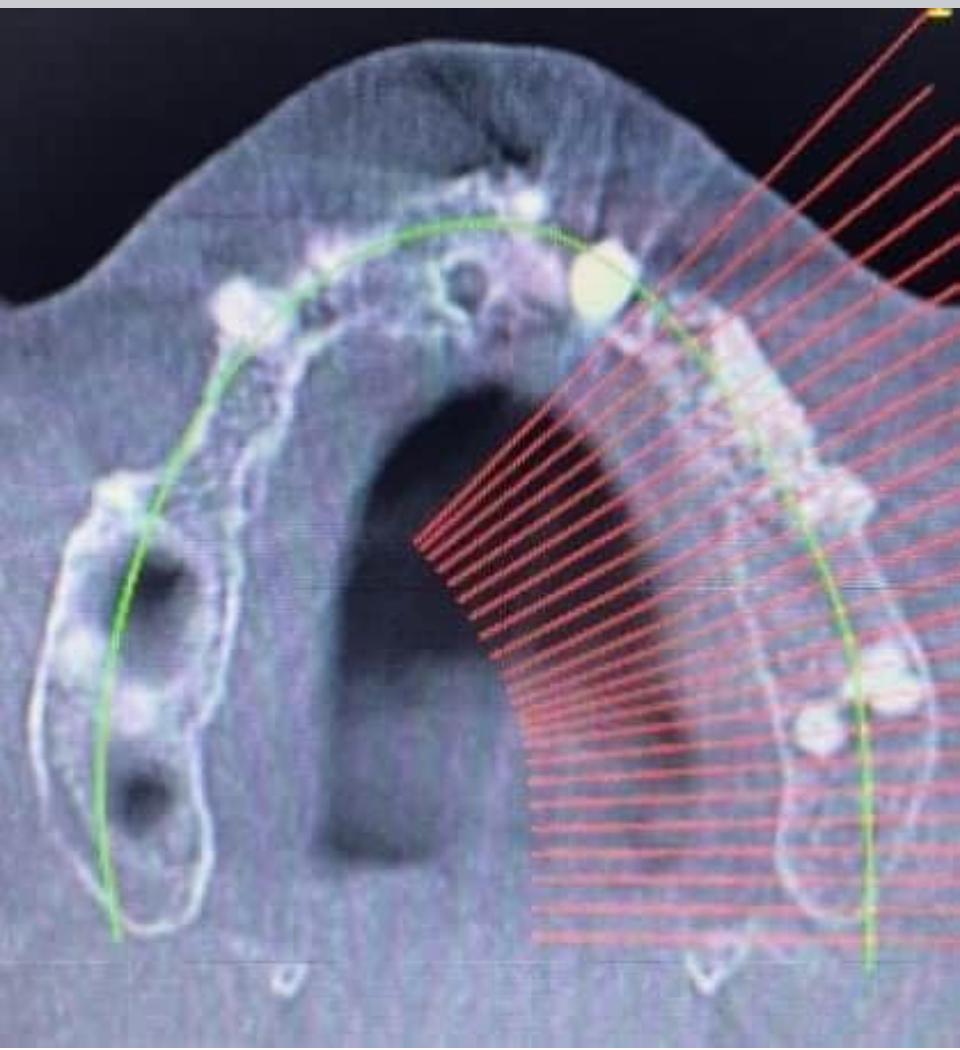

La rigenerazione ossea guidata (GBR) dell’emiarcata sinistra superiore è una procedura chirurgica utilizzata per aumentare il volume osseo in un’area specifica della mascella, preparando il sito per un futuro posizionamento implantare. Questo intervento prevede l’utilizzo di innesti ossei (autologhi, sintetici o eterologhi) e di membrane protettive che guidano la crescita dell’osso nella zona desiderata. Le immagini TAC forniscono una valutazione dettagliata della quantità di osso presente e della necessità di rigenerazione, permettendo di pianificare l’intervento con precisione per garantire un risultato ottimale.